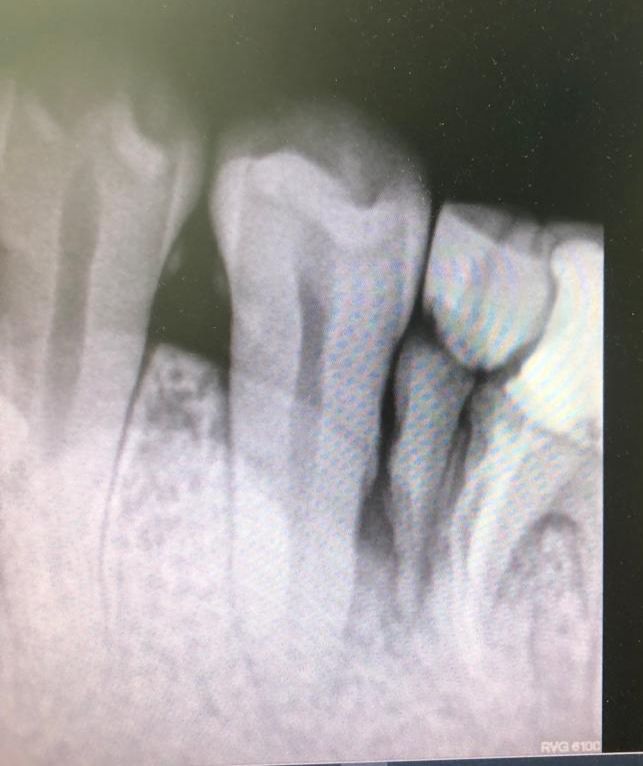

Pasado un tiempo se le cita para tallar el muñón de la raíz distal, que ha tenido una buena evolución una vez separada de la raíz anterior infectada.

En la misma sesión se le instala el hilo de retracción, para la toma de impresiones con siliconas. También diseñamos una corona de circonio multilayer, la cual se le cementa al cabo de una semana. Esta corona de circonio se deja muy suave de oclusión para que no sea presionada por las fuerzas de masticación y bruxismo, porque tendría más tendencia a la fractura.